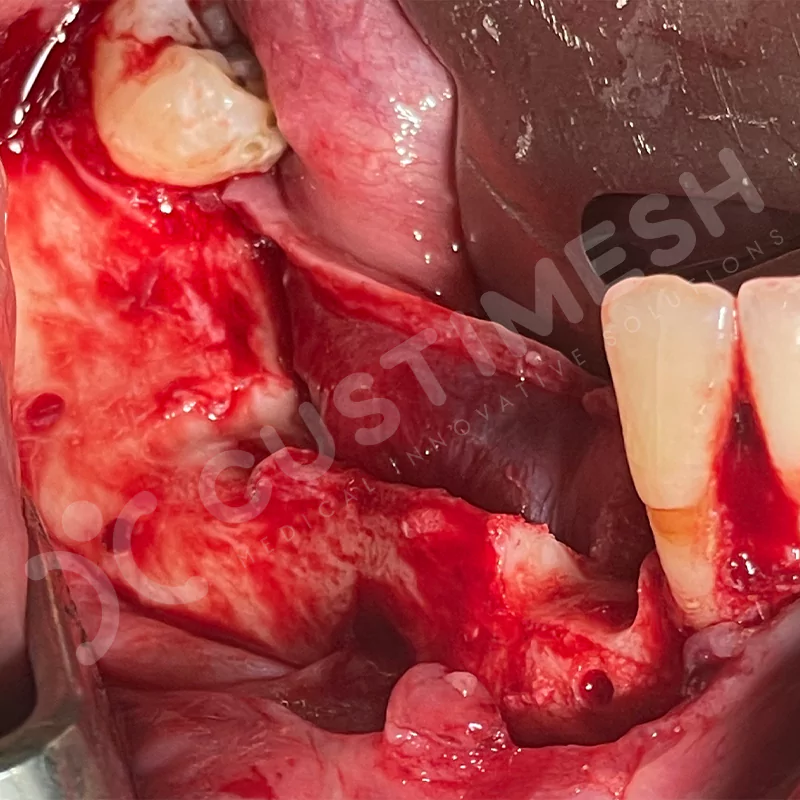

Modern diş hekimliğinde, çene gelişimini tamamlamamış veya ciddi kemik kaybı yaşayan hastalar için kişiye özel titanyum implantlar ile çözüm bulunmaktadır. CAD/CAM teknolojisi ve lazer sinterleme yöntemiyle üretilen bu implantlar, hastanın bireysel anatomik yapısına tam uyum sağlayarak geleneksel implantların uygulanamadığı vakalarda mükemmel bir alternatif oluşturmaktadır. Özellikle ileri derecede kemik kaybı olan hastalar için geliştirilen subperiosteal implantlar, periostun altına yerleştirilerek minimal invaziv bir yaklaşım sunarken, bilgisayarlı tomografi verileri ve sonlu eleman analizleriyle optimize edilmiş tasarımları sayesinde hem estetik hem de fonksiyonel sonuçlar garanti etmektedir. Bu yenilikçi teknoloji, tek seansta implant ve protez uygulamasına imkan vererek hastaların aynı gün doğal gülüşlerine kavuşmalarını sağlarken, kemik greftleme gibi ek işlem ihtiyacını ortadan kaldırarak cerrahi süreci büyük ölçüde kolaylaştırmaktadır. Kişiye özel tasarımı ve üstün biyouyumluluğu sayesinde, daha önce tedavisi mümkün görülmeyen kompleks vakalarda bile başarılı sonuçlar sunan bu implantlar, modern diş hekimliğinde yeni bir çağ açarak hastaların yaşam kalitesini artırmayı hedeflemektedir.

VAKA 2